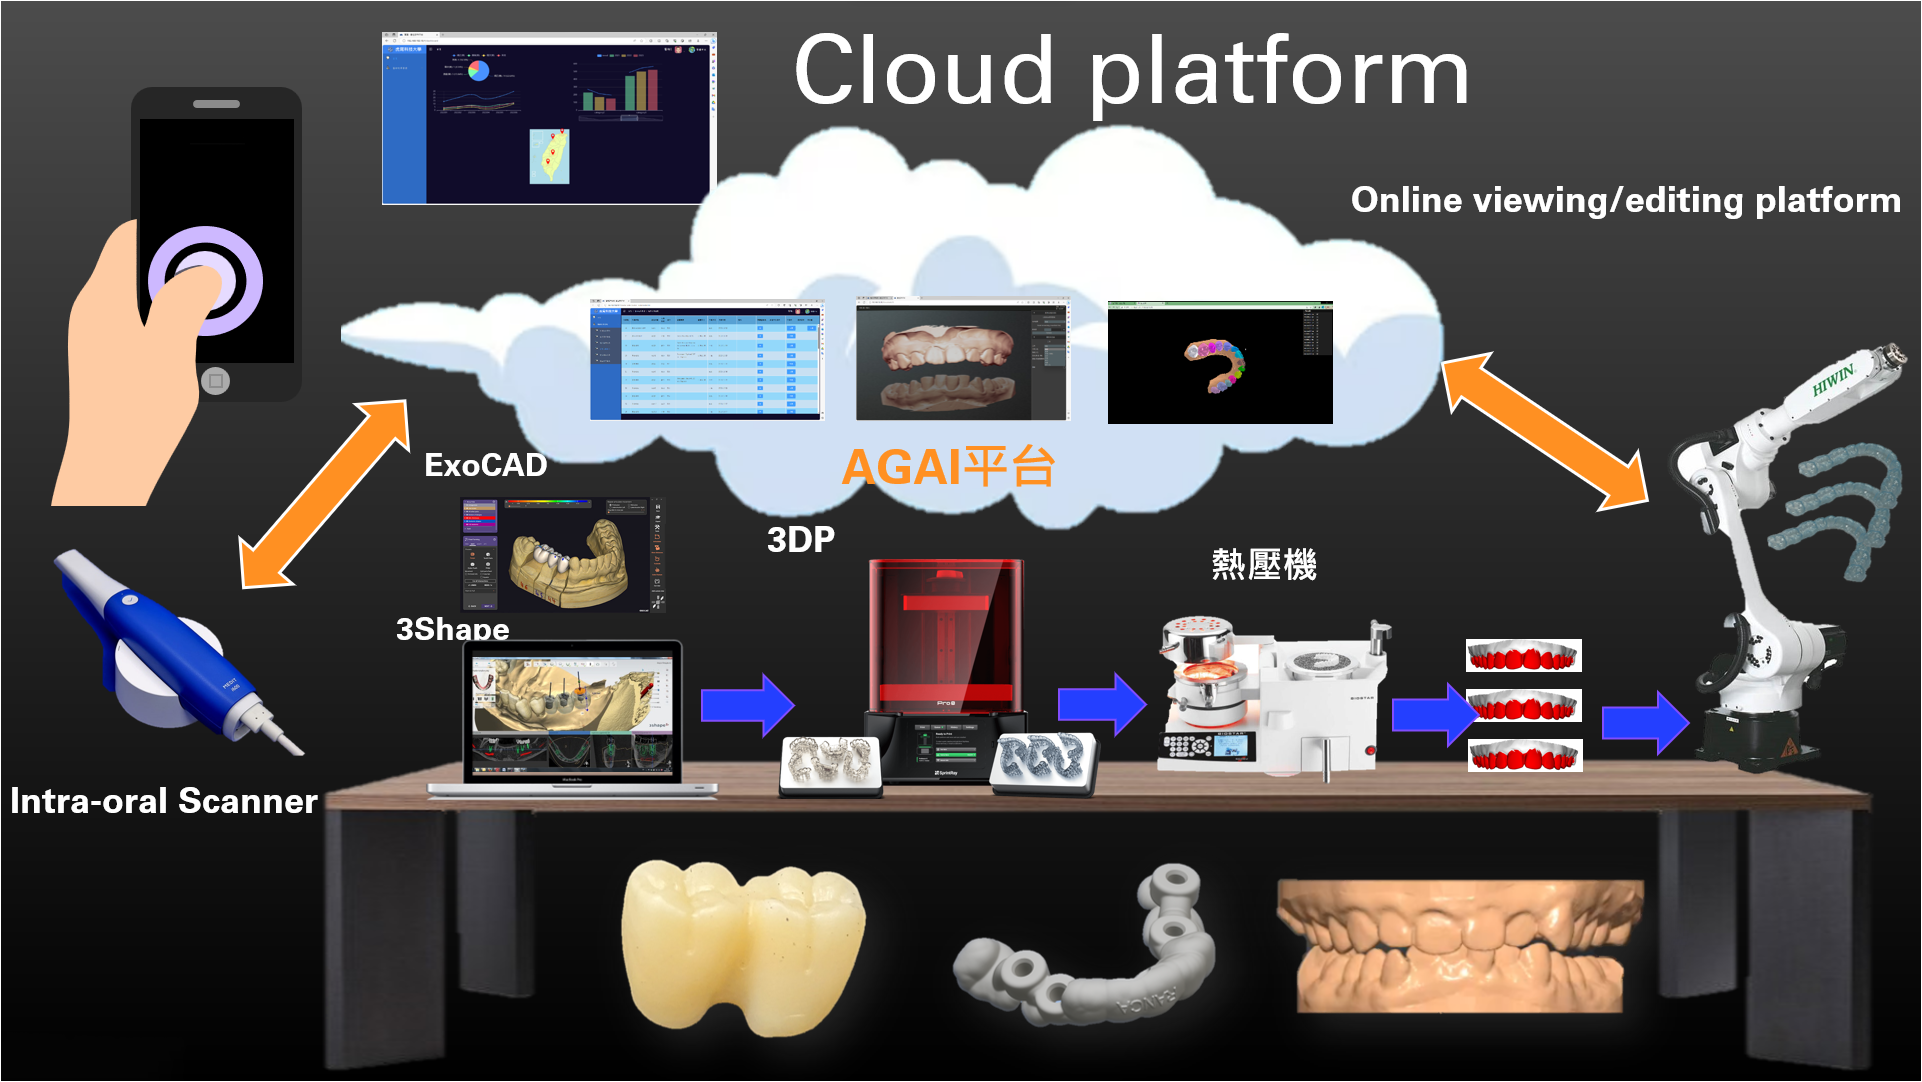

One-stop dental cloud platform:

Query/Simulate

One-stop dental cloud platform:

Upload/View

One-stop dental cloud platform:

AI separation/extraction

一站式牙科雲端平台:

線上編輯

One-stop dental cloud platform:

View anytime

Traffic estimate (one year)

There are 1,000 clinics in total, and the order for each clinic is as follows:

1. Denture orders 50 pieces/M

2. Dental implant orders: 10 orders/M

3. Correction orders 10 times/M

Therefore, the total traffic of 1000 clinics is estimated as follows:

- Dentures (STL): 192T/Y

- Dental implant (STL, CT, JPG): 36T/Y

- Correction (STL, JPG): 204T/Y

Total flow: 432T/Y